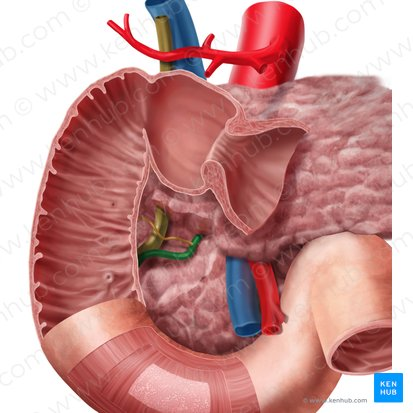

Hepatic Artery

A branch of the celiac artery that supplies oxygenated blood to the liver.

Hepatic Portal Vein

A large vein that carries deoxygenated but nutrient-rich blood from the digestive organs (stomach, intestines, spleen, pancreas) to the liver for processing.

Inferior Vena Cava

A large vein that carries deoxygenated blood from the lower and middle body back to the heart.

Right Hepatic Duct

A duct that carries bile produced by the right lobe of the liver.

Left Hepatic Duct

A duct that carries bile produced by the left lobe of the liver.

Common Hepatic Duct

The duct formed by the union of the right and left hepatic ducts, which carries bile away from the liver.

Cystic Duct

The duct that connects the gallbladder to the common hepatic duct, allowing bile to enter and exit the gallbladder.